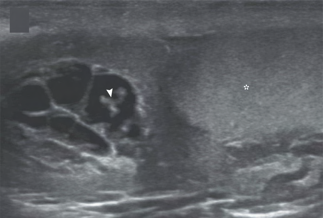

Recent studies indicate that Generative Pre-trained Transformer 4 with Vision (GPT-4V) outperforms human physicians in medical challenge tasks. However, these evaluations primarily focused on the accuracy of multi-choice questions alone. Our study extends the current scope by conducting a comprehensive analysis of GPT-4V's rationales of image comprehension, recall of medical knowledge, and step-by-step multimodal reasoning when solving New England Journal of Medicine (NEJM) Image Challenges - an imaging quiz designed to test the knowledge and diagnostic capabilities of medical professionals. Evaluation results confirmed that GPT-4V outperforms human physicians regarding multi-choice accuracy (88.0% vs. 77.0%, p=0.034). GPT-4V also performs well in cases where physicians incorrectly answer, with over 80% accuracy. However, we discovered that GPT-4V frequently presents flawed rationales in cases where it makes the correct final choices (27.3%), most prominent in image comprehension (21.6%). Regardless of GPT-4V's high accuracy in multi-choice questions, our findings emphasize the necessity for further in-depth evaluations of its rationales before integrating such models into clinical workflows.